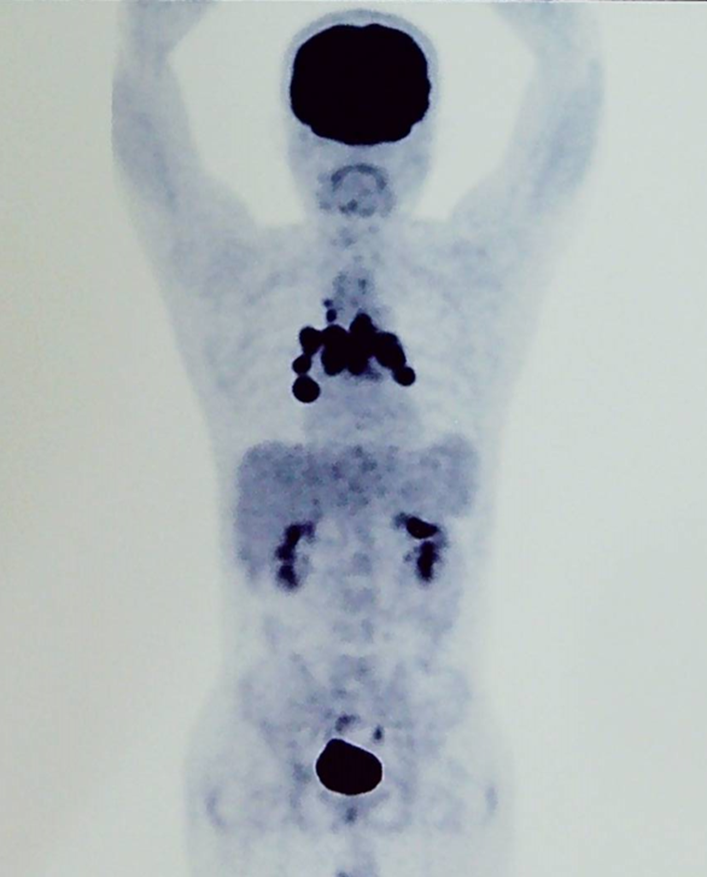

诊断明确后,患者立即开始接受化疗,前三个疗程采用了 R-CHOPE 为主的化疗,考虑到患者中枢神经系统受累及风险较高,中间加入了高剂量甲氨蝶呤 1 疗程进行中枢防控,同时还联合了来那度胺等靶向药物治疗,3 疗程后患者症状缓解,PET-CT 评估达到了部分缓解。进而患者继续接受了 3 疗程 R-CHOPE 及高剂量甲氨蝶呤的化疗。

不幸的是,患者的疗效并没有进一步提高,反而在上述治疗后的 PET 评估中出现了疾病进展,如下图 2: